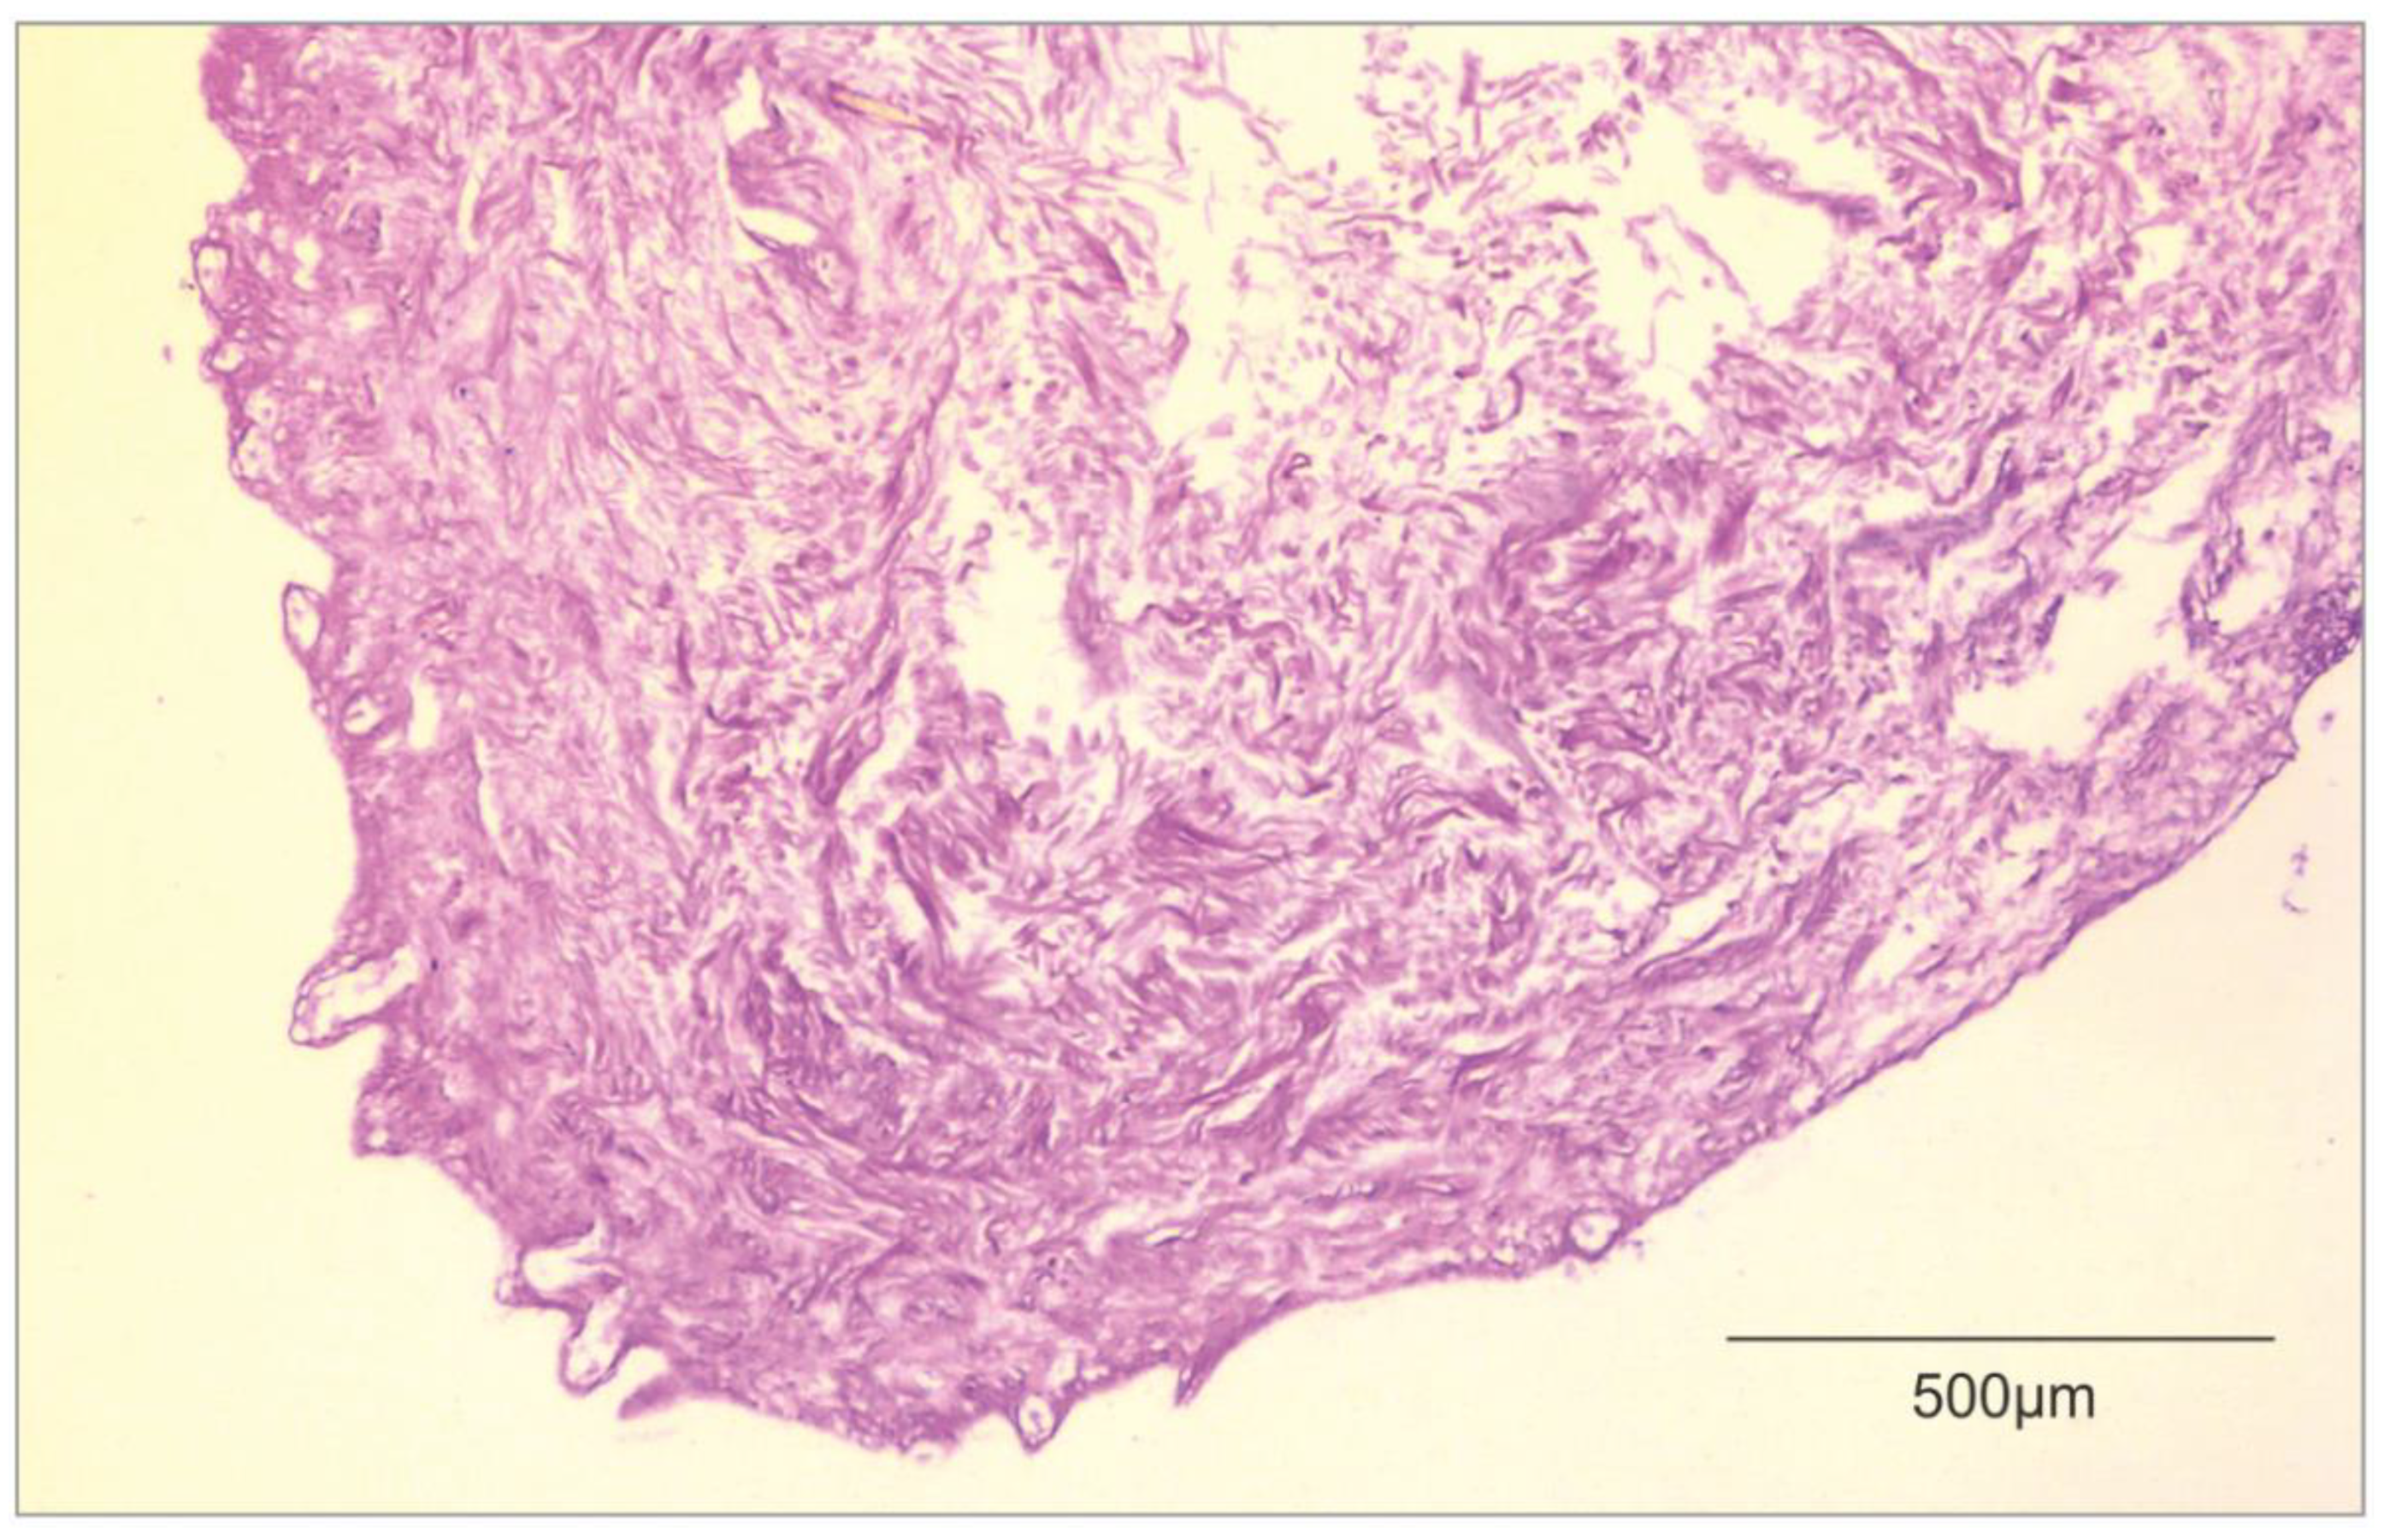

2. Decellularization of Human Allogeneic Skin